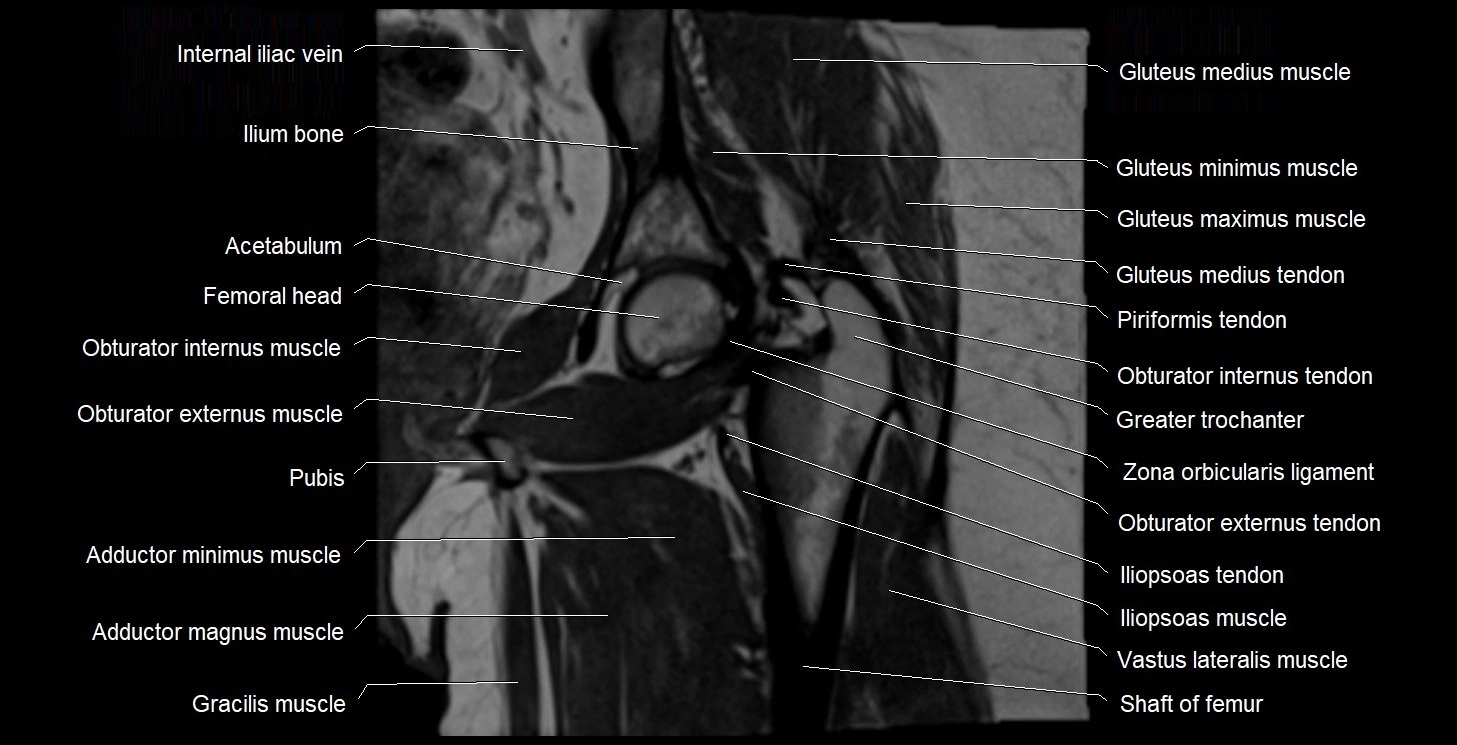

- Acetabulum

- Body of ischium

- Gluteus medius muscle

- Gluteus minimus muscle

- Greater trochanter

- Head of femur

- Neck of femur

- Obturator internus muscle

- Obturator internus tendon

- Pubococcygeus muscle

- Transverse acetabular ligament

- Zona orbicularis ligament